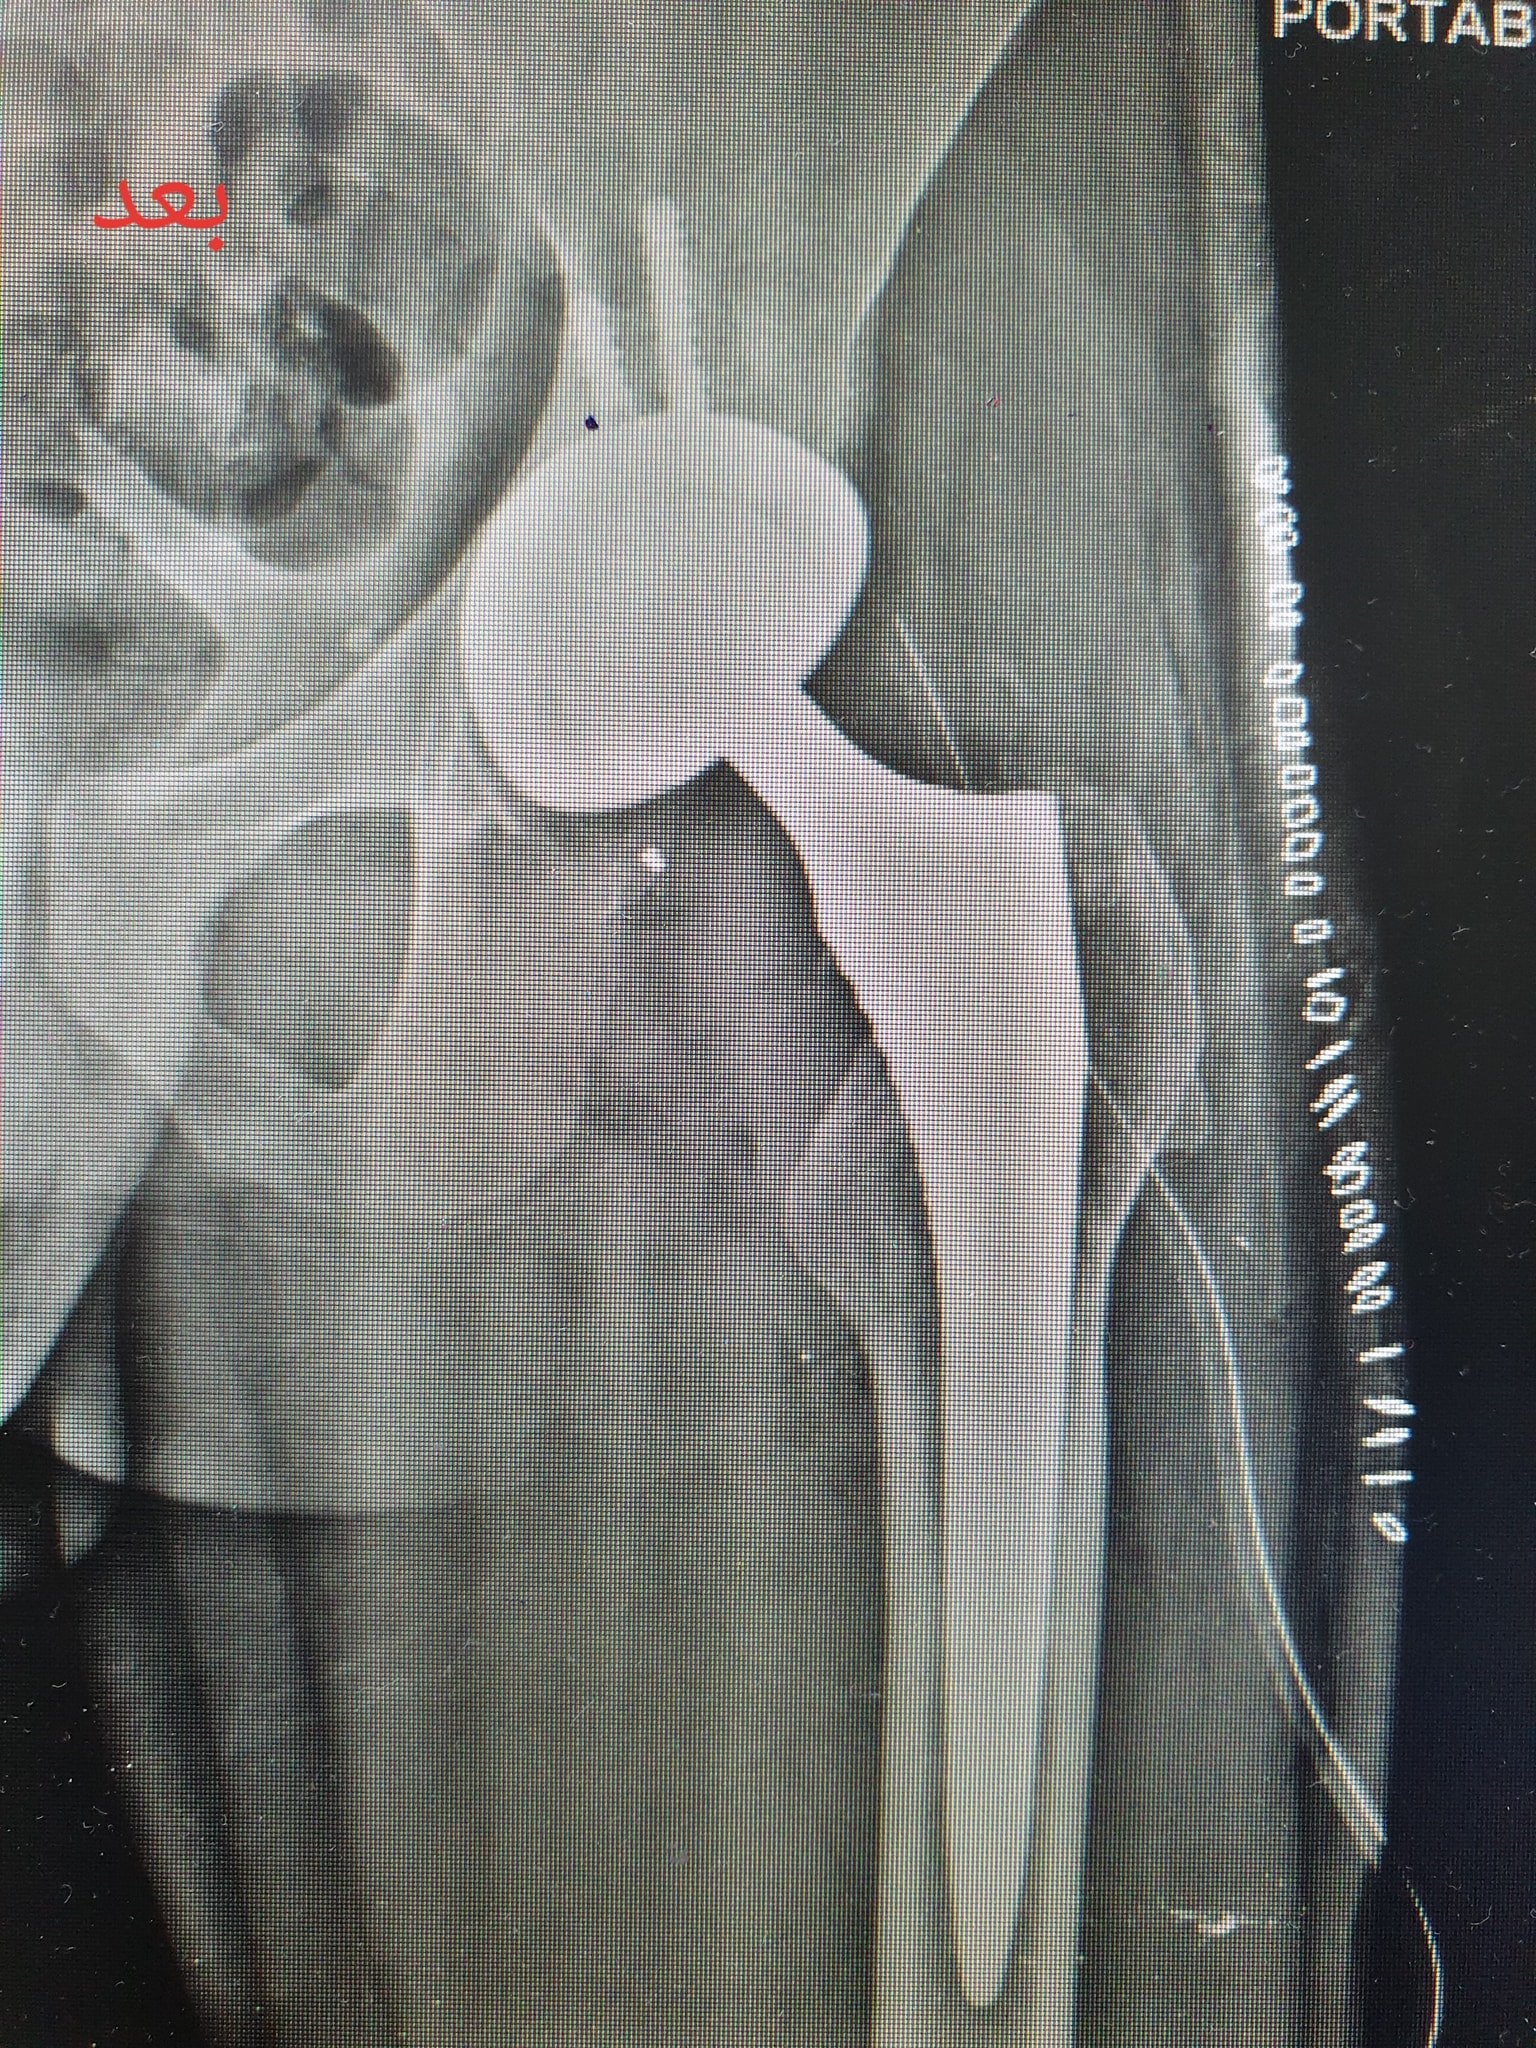

زراعة المفاصل الصناعية ورك و